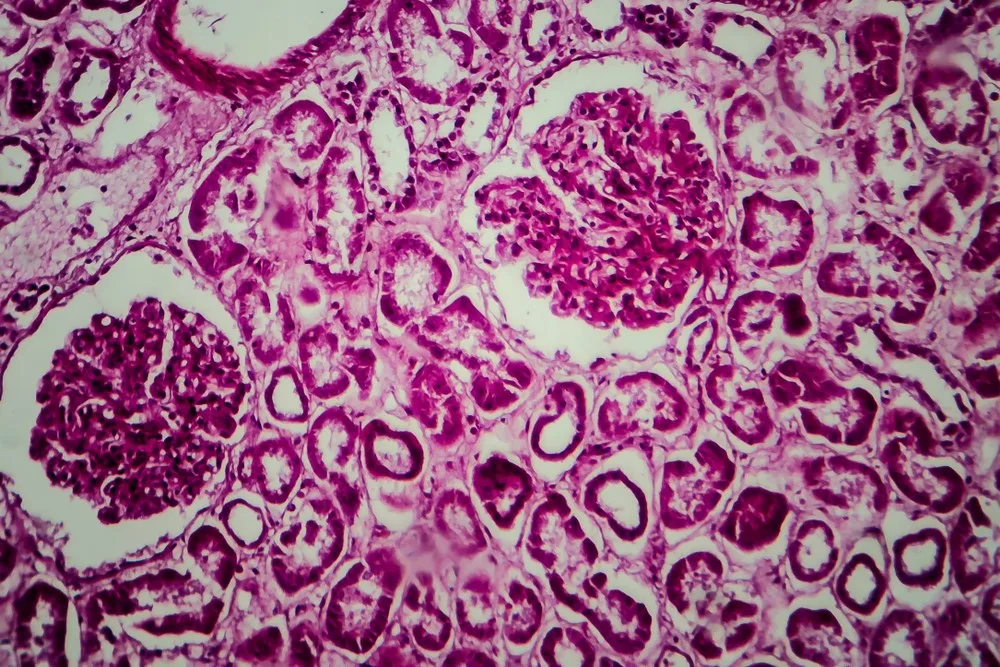

- Βιοψία νεφρού. Σε αυτή την εξέταση, αφαιρούνται δείγματα ιστού από το νεφρό και ελέγχονται στο μικροσκόπιο.